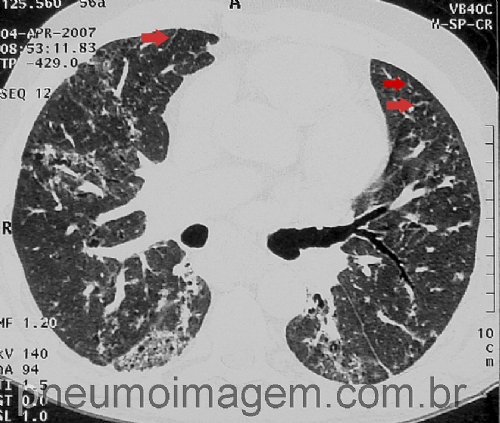

Para ver imagens sobre doença intersticial associada à Esclerose Sistêmica,

clique aqui.